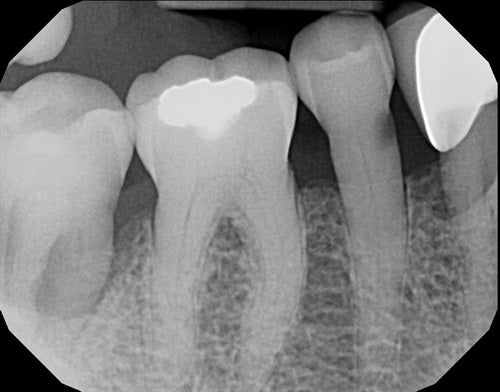

Dahl technique Doc Terry style by Dr. Ahmad Fayad

Introduction: 40 year old female on a tight budget and is slowly losing her teeth. She was referred to me by another patient who had the same style buildups. Decided... Read More